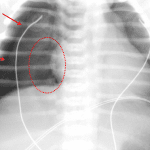

Indication: Meconium aspiration

- Large right and small left pneumothoraces

- Leftward shift of the cardiothymic silhouette

- Minimal retrocardiac airspace opacification

- Pneumothorax

Large right and small left pneumothoraces. Leftward shift of the cardiothymic silhouette raises concern for associated tension physiology.

Minimal retrocardiac airspace opacification, which may relate to atelectasis or aspiration.